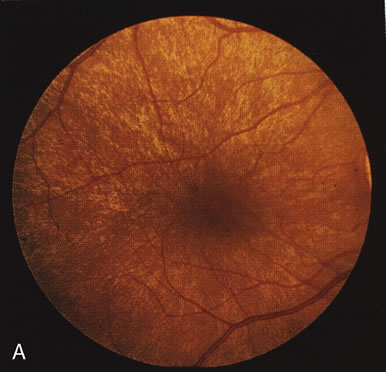

The carrier female with XLR RP, who has the golden tapetal sheen reflex, has normal FA findings. This suggests that the abnormal reflex is not due an abnormal pigment layer or deposition7 (Fig. 2A and B).

In Oguchi's disease the hallmark fundus finding is a yellow metallic sheen (Fig. 2C). A similar sheen has been seen in progressive cone dystrophies and juvenile macular degeneration.7 In all these diseases the abnormal reflex does not affect the normal transmission of fluorescein dye (Fig. 2D). The normal FA suggests that, like findings in the carrier female in XLR RP, the abnormal retinal reflex in this disease is unrelated to pigment concentration or distribution.